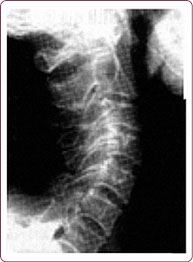

Чаще всего этот физиологический изгиб гипертрофируется, и шейные позвонки «проваливаются» вглубь шеи – формируется гиперлордоз шейного отдела позвоночника, зажимая нервные окончания и перекрывая кровоснабжение мозга (рис. 4, 5).

Рис. 4. Гиперлордозный изгиб шейного отдела позвоночника